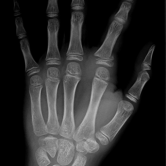

Röntgenbilder